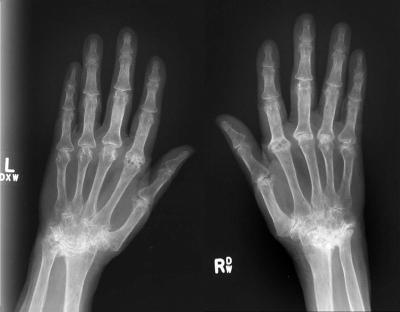

Scientists have identified a new protein (C5orf30) which regulates the severity of tissue damage caused by rheumatoid arthritis (RA), an autoimmune disease that causes inflammation, pain, stiffness and damage to the joints of the feet, hips, knees, and hands.

Rheumatoid arthritis is the most common inflammatory of the types of arthritis affecting around 1% of the population. It is estimated that 30% of patients with rheumatoid arthritis are unable to work within 10 years of onset of the condition. It affects more women than men, and often more severely. It is also most common between the ages of 40 and 70, but it can affect people of any age including children.

One of the biggest difficulties with treating the condition is early diagnosis. With early diagnosis and aggressive treatment, it is possible to reduce the damage to the joints caused by RA. Deciding the most appropriate treatment for each patient at the earliest possible stage is central to effectively tackling the condition.